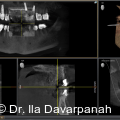

Die moderne Implantologie vereint heute funktionelle Stabilität mit höchsten ästhetischen Ansprüchen. Gerade im Frontzahnbereich hängt der Behandlungserfolg entscheidend von der präzisen Planung, der gewebeschonenden chirurgischen Umsetzung und einer frühzeitigen prothetischen Integration ab. Fotos: © Dr. Ila Davarpanah